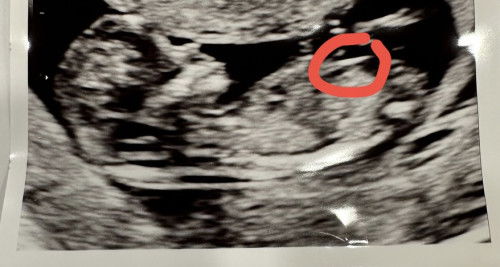

Which week are you in ? If below 18 weeks still hard to confirm as previously gynae told me i might be expecting a girl but during detailed scan its a boy

Looks like a girl